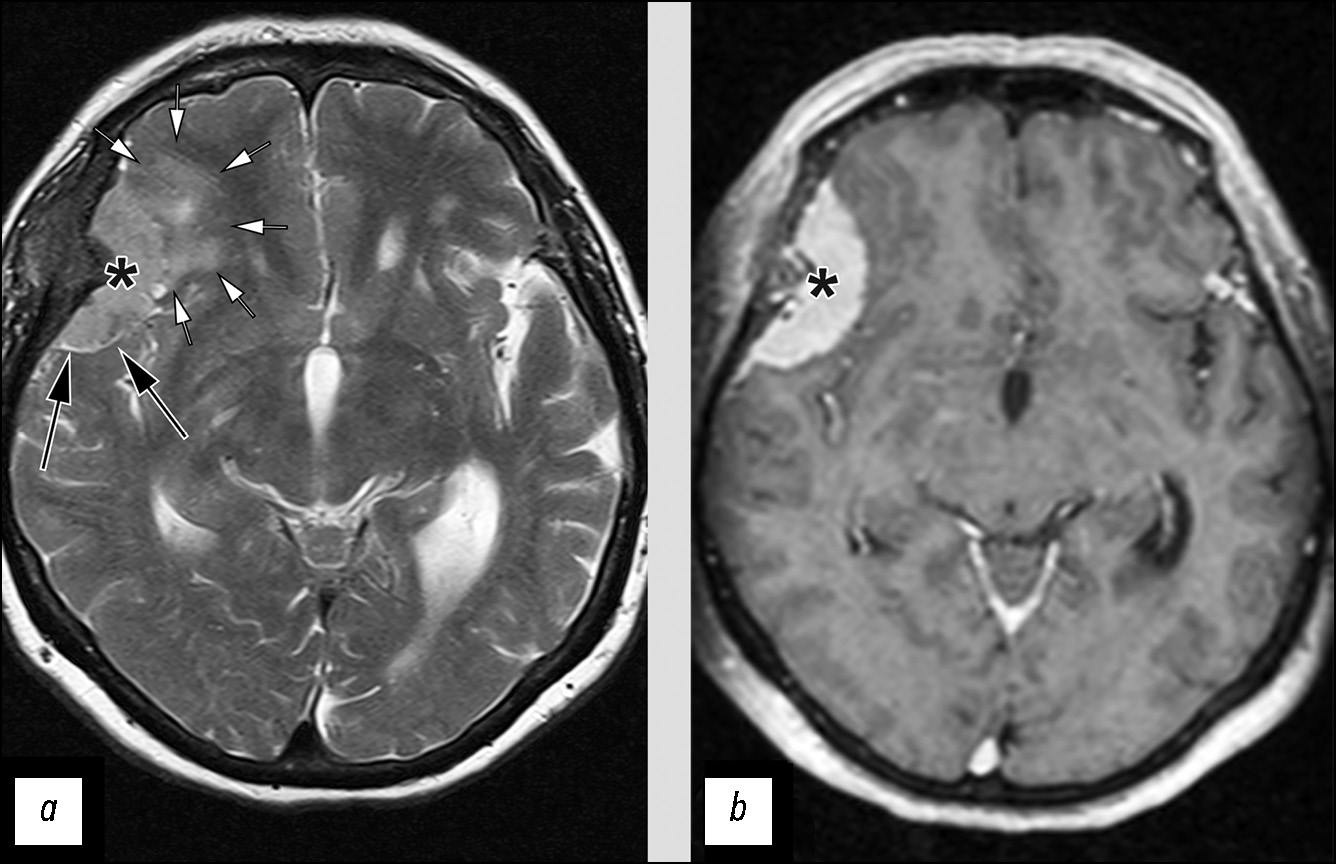

Инструментальная диагностика. По данным МРТ (рис. 6, a), в левом мостомозжечковом углу определяется внемозговое образование размерами 2,8×2,6×2,1 см, неоднородной структуры с выраженным, но гетерогенным контрастированием. Признаков распространения опухоли во внутренний слуховой проход или вовлечения черепных нервов достоверно не определяется.

Рис. 6. Сложность определения взаимосвязи опухоли с черепным нервом или мозговой оболочкой: a — невринома с отсутствием визуальной взаимосвязи с черепными нервами (стрелкой показаны «интактные» VII и VIII нервы во внутреннем слуховом проходе); b — менингиома с признаками связи опухоли с черепными нервами (стрелка).

Дифференциальная диагностика. Данное образование при наличии типичных для неврином проявлений (структура и форма опухоли) из-за отсутствия чёткой взаимосвязи с черепными нервами, было ошибочно идентифицировано как менингиома.

Лечение. Пациентке выполнена резекция опухоли, гистологическое заключение: вестибулярная шваннома, С72.4 9560/01.

Инструментальная диагностика. На сериях МРТ-изображений (рис. 6, b) в левом мостомозжечковом углу определяется внемозговое образование однородной структуры и гомогенным контрастированием, размерами до 3,4×2,5×3,0 см. Опухоль распространяется во внутренний слуховой проход. Левые седьмой и восьмой черепные нервы на фоне новообразования не определяются.

Дифференциальная диагностика. Наличие взаимосвязи опухоли с черепными нервами, по всей видимости, послужило решающим фактором для неверной классификации данного образования как невриномы. Нужно отметить, что выявленная опухоль имеет признаки, характерные для менингиом (однородная структура перед контрастированием и после, широкое прилежание к твёрдой мозговой оболочке).

Лечение. Пациентке выполнена резекция опухоли, гистологическое заключение: менингиома (Grade 1), С70.0 9530/01.